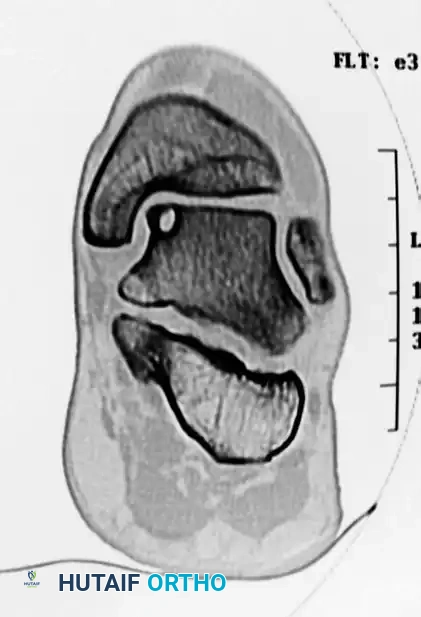

PREOPERATIVE PLANNING AND IMAGING

Thorough preoperative imaging is mandatory to define the lesion's morphology, depth, and precise anatomical location.

- Weight-Bearing Radiographs: Standard anteroposterior (AP), lateral, and mortise views evaluate overall joint space, alignment, and the presence of osteophytes.

- Computed Tomography (CT): CT is the gold standard for evaluating the osseous architecture, identifying subchondral cysts, and determining the exact dimensions of the bony defect.

- Magnetic Resonance Imaging (MRI): MRI is essential for assessing the integrity of the overlying articular cartilage, identifying bone marrow edema, and evaluating concomitant soft tissue injuries (e.g., lateral ligamentous complex tears).